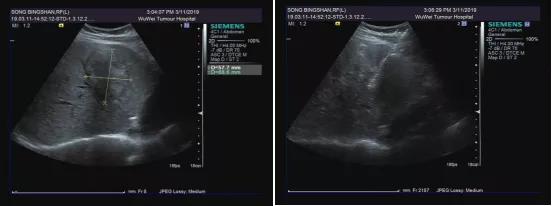

05超声引导下肿物/结节射频消融术肝脏肿物、甲状腺结节、乳腺结节均可在超声引导下,经皮肤穿刺,将电极针直接刺入肿瘤组织中。在高频交变电流作用下,造成肿瘤细胞凝固性坏死,进而达到彻底杀灭肿瘤的目标。

我院超声科医师正在进行肝脏肿物射频消融术